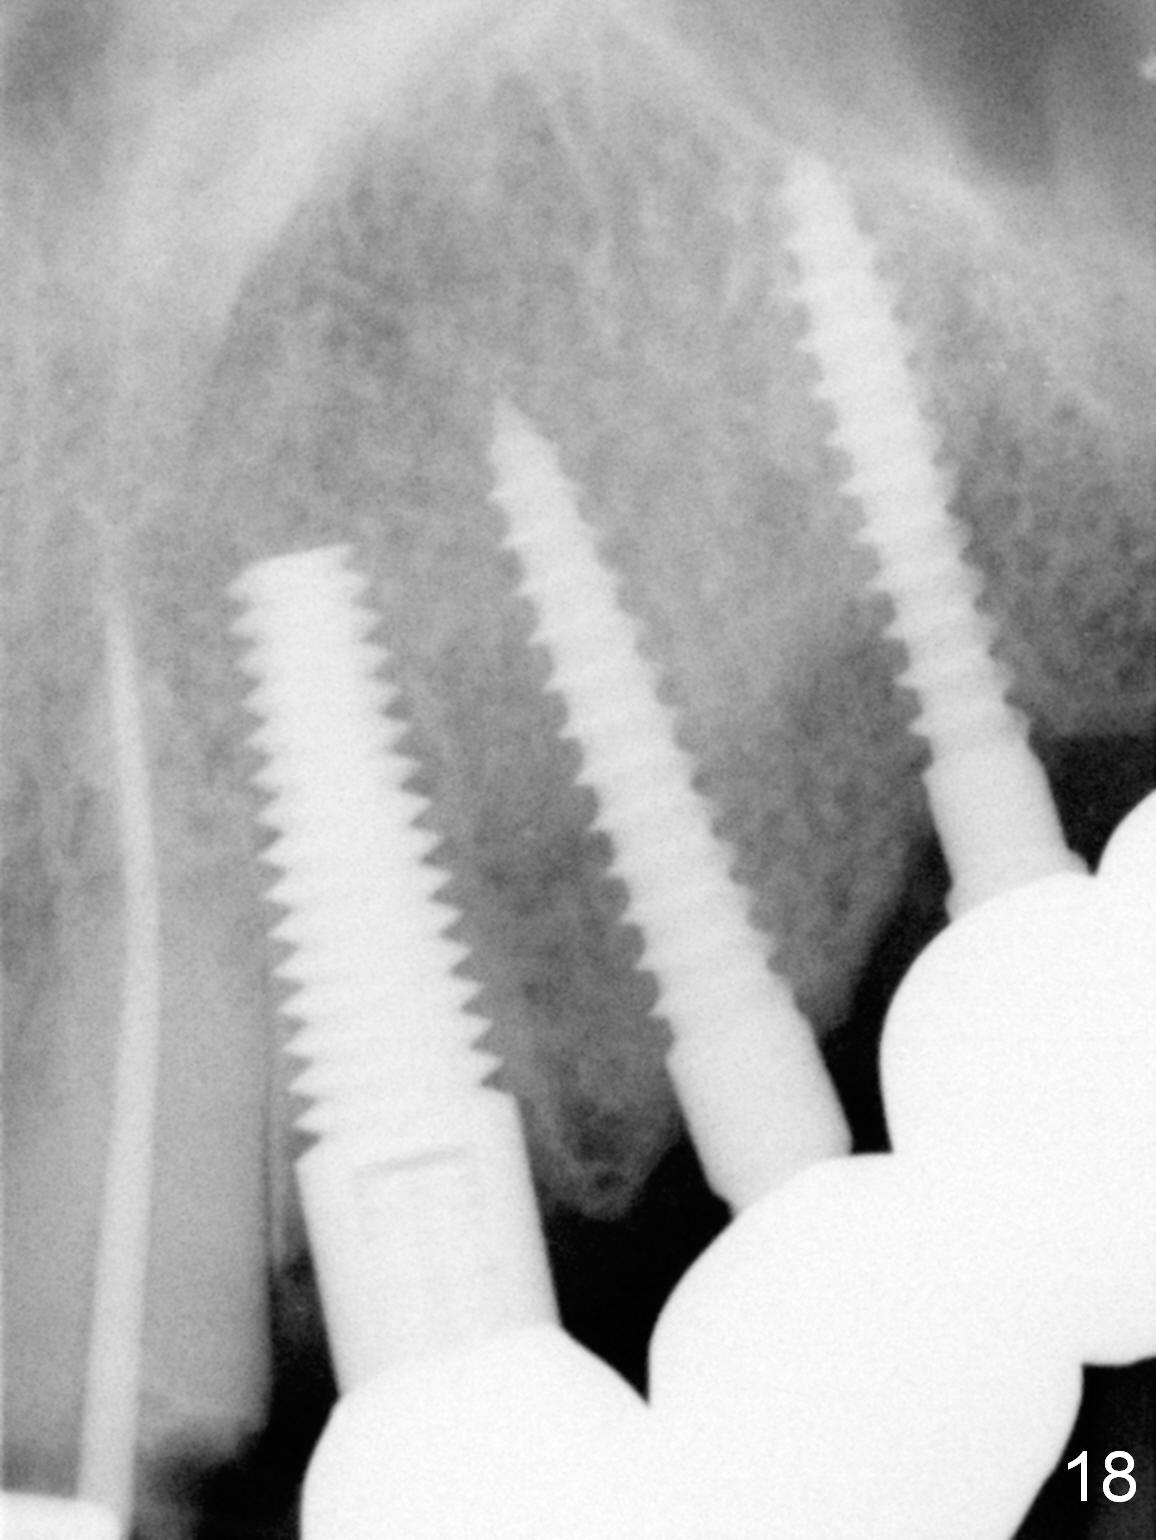

Six months post cementation, the tooth #9 becomes symptomatic. Is it possible that the implant at #10 is too close to the root of #9? It is asymptomatic after pulpotomy, but the tooth fractures equi/supragingivally. Two PAs taken while RCT show osteointegration at #10-12 (Fig.18,19). While the bone density increases at #10 regular implant, there is minimal bone loss around the 1-piece implants 13 months post cementation (18 months postop, Fig.20,21). The gingiva remains healthy 19 months post cementation (Fig.22). 76岁病人突然打电话说一个植牙牙冠松动,其实9号牙(自然牙)折裂,6,10-13号牙植牙好像没有骨质吸收(图二十三至二十五),10-13牙位牙龈健康(图二十六,行使功能五年)。9号牙牙冠重新粘固后,显示前牙深覆合,深覆盖(图二十七,二十八)。如果再次脱落需要植牙,选择一段式有助于植入和修复,因为植体和基台直径小。两段式植牙相对基台直径至少4,或者4.5毫米,前牙修复显得笨重。由于9,10牙根和植体接近,9号牙植体需要偏小而长,3x14或者15毫米(图二十九)。